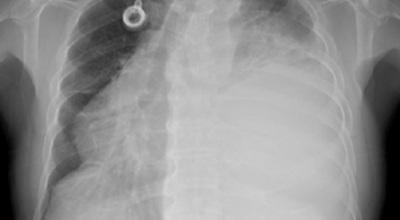

폐암 검사는 X-ray를 통해서 검사하는데 , 크기가 작거나 구석에 위치한 경우 확인이 어려운 경우도 있습니다. 그리고 조직 검사를 통해서 정확한 진단을 하게 돼요. 폐암이 발견되면 종양의 크기나 전이 여부 , 위치에 따라서 수술 여부를 결정하게 돼요.